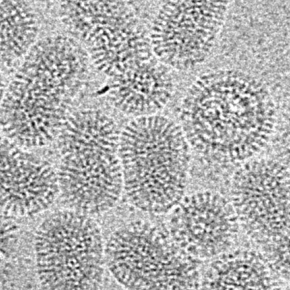

Les virus influenza, responsables de la grippe, détournent un grand nombre de machineries cellulaires de l’hôte pour mener leur cycle infectieux. L’étude de ces multiples interactions entre virus et cellules est indispensable pour mieux comprendre les mécanismes d’infection et identifier de nouvelles stratégies thérapeutiques. Cette étude, publiée dans Journal of Virology, a mis en lumière un nouveau mécanisme de détournement viro-induit du facteur de transcription p53.

Les virus influenza constituent un problème majeur de santé publique, avec un impact important sur les populations à risque, lors d’épidémies saisonnières. De nombreuses équipes de recherche s’intéressent aux interactions entre les virus influenza et la cellule hôte, afin de mieux comprendre les mécanismes sous-jacents lors de l’infection. Les virus influenza sont connus pour moduler la réponse de la cellule cible afin de favoriser leur réplication, et ainsi échapper à la réponse immune. Pour y parvenir, les virus influenza possèdent une protéine non-structurale nommée NS1, véritable « couteau-suisse », qui joue un rôle central dans la modulation de la réponse antivirale, mais aussi la régulation de plusieurs voies de signalisation, via son interaction avec différentes protéines cellulaires. L’une de ces protéines, p53, est une protéine régulatrice centrale impliquée dans un très grand nombre de mécanismes cellulaires, comme la régulation du cycle cellulaire, l’apoptose ou encore la sénescence. Ce facteur de transcription, dont on célèbre cette année les 40 ans de la découverte, a majoritairement été étudié dans le domaine de l’oncologie et des virus oncogènes. Cependant, on sait que p53 est également impliqué dans le contrôle des infections virales, tous les virus ayant développé une large palette de stratégies différentes pour moduler/détourner les fonctions de p53, et ce pour se répliquer de manière optimale dans la cellule hôte.

Après avoir précédemment montré que la stabilité et l’activité transcriptionnelle de p53 était finement modulée au cours de l’infection par les virus influenza, avec l’implication de la protéine virale NS1 à différents niveaux, les chercheurs, en collaboration avec des équipes de recherche du CRCL (Lyon), de l’université Laval (Québec) et de l’université de Dundee (UK), ont mis en évidence un nouveau mécanisme de détournement viro-induit des fonctions de p53. En combinant des approches de virologie classique et de biologie cellulaire, et en utilisant des outils initialement développés pour l’étude de p53 dans les cancers, ils ont démontré le rôle de la protéine virale NS1 dans la modulation de l’épissage du gène TP53, via le facteur cellulaire CPSF4. Cette modulation viro-induite des isoformes de p53 issues de l'épissage a pour conséquence une modulation de l'activité transcriptionnelle de p53, et notamment la réponse antivirale de type Interféron. Ces travaux ouvrent de nouvelles perspectives de recherche pour mieux comprendre la biologie des virus influenza.